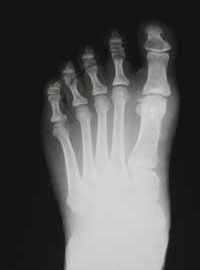

CHIRURGIA DEL PIEDE: diabetico, alluce valgo, dita a martello, neuroma di Morton.